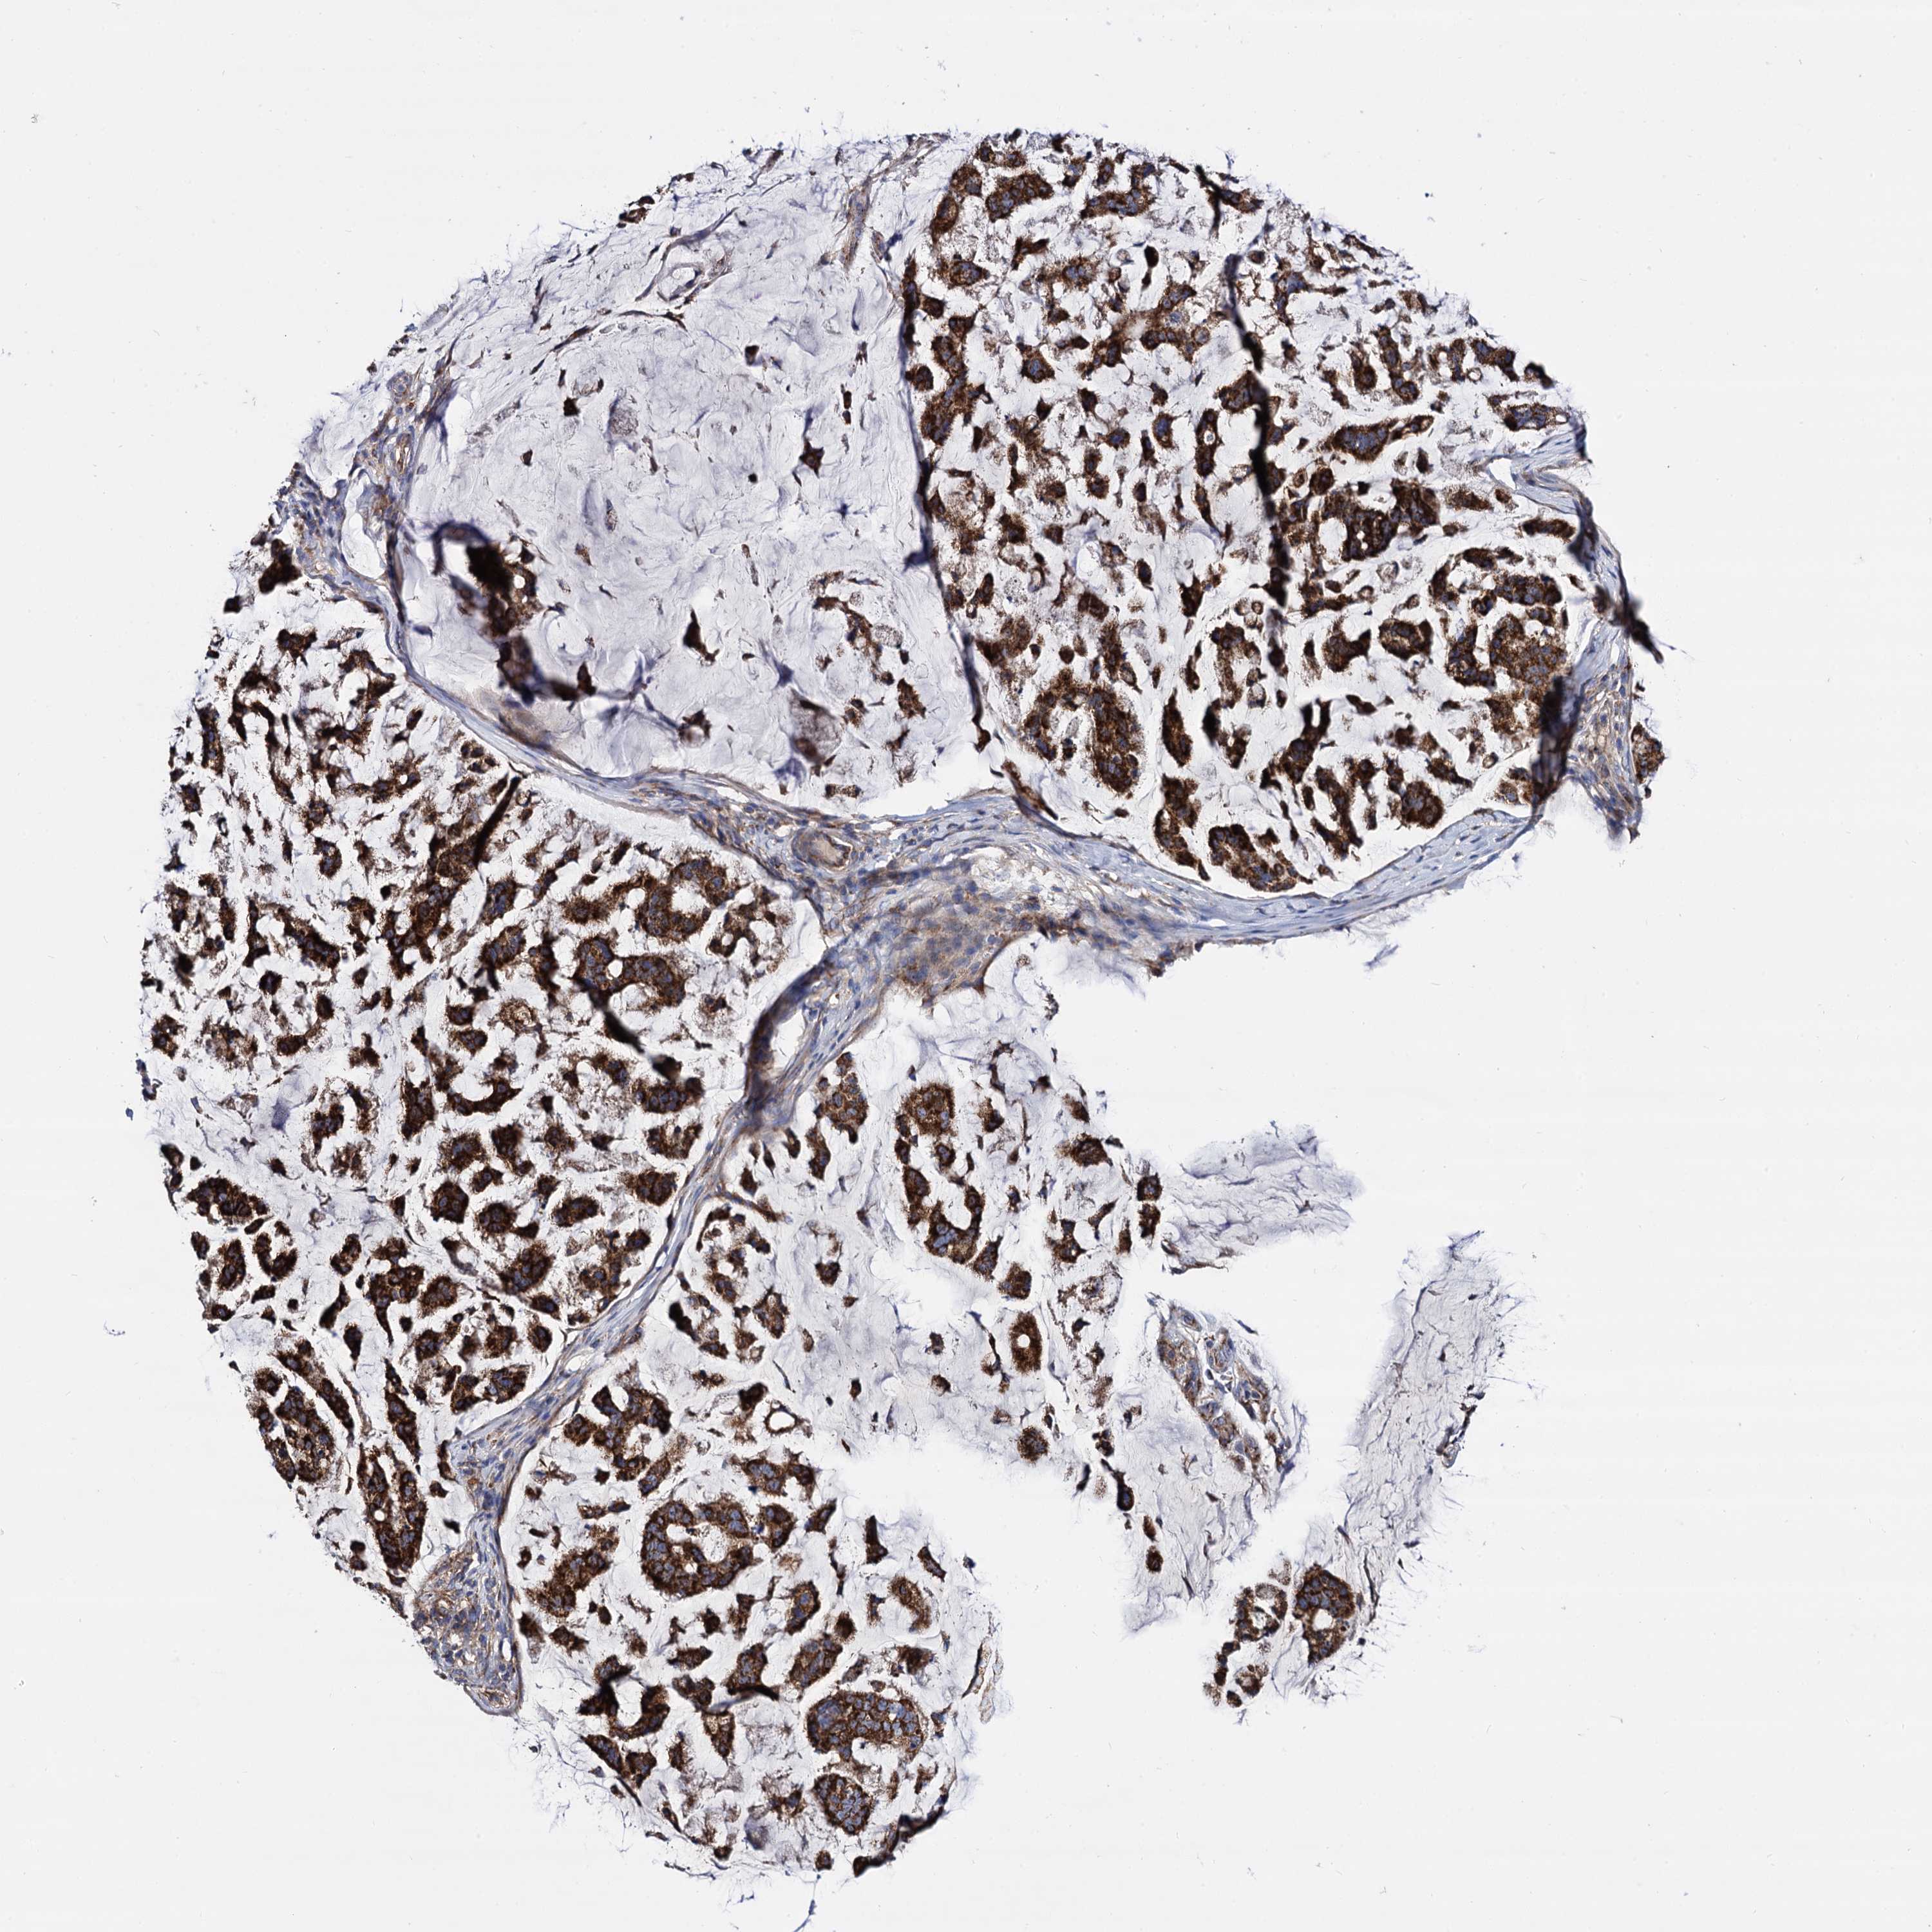

STOMACH CANCER - Protein expressioni

A mouse-over function shows sample information and annotation data. Click on an image to view it in a full screen mode. Samples can be filtered based on level of antibody staining by selecting one or several of the following categories: high, medium, low and not detected. The assay and annotation is described here.

Note that samples used for immunohistochemistry by the Human Protein Atlas do not correspond to samples in the TCGA dataset.

Antibody stainingi

Antibody staining in the annotated cell types in the current human tissue is reported as not detected, low, medium, or high, based on conventional immunohistochemistry profiling in selected tissues. This score is based on the combination of the staining intensity and fraction of stained cells.

Each image is clickable and will lead to virtual microscopy that enables deeper exploration of all samples and also displays staining intensity scores, fraction scores and subcellular localization as well as patient and tissue information for each sample.

Antibody HPA040845

Staining

High

Medium

Low

Not detected

Intensity

Strong

Moderate

Weak

Negative

Quantity

>75%

75%-25%

<25%

None

Location

Nuclear

Cytoplasmic/membranous

Cytoplasmic/membranous,nuclear

Adenocarcinoma, NOS